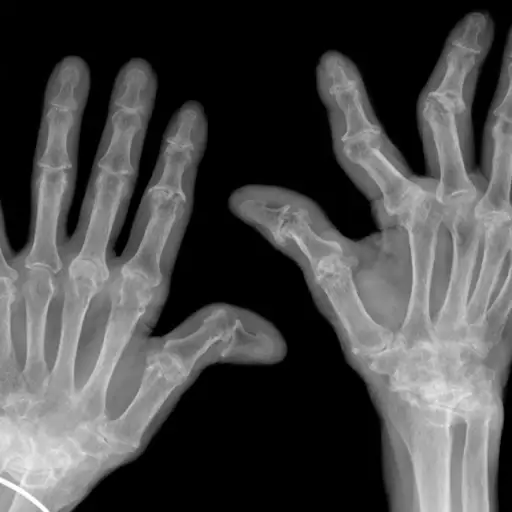

事实:骨关节炎是一种“磨损”退行性关节疾病;联合疼痛全天增加。RA和银屑病关节炎都是自身免疫疾病,免疫系统攻击关节;在早晨,关节疼痛往往是更糟。银屑病关节炎和RA可能难以区分。银屑病关节炎很少对称,而RA是。风湿病学家还测试了类风湿因素,有时有时可以帮助实现正确的诊断。